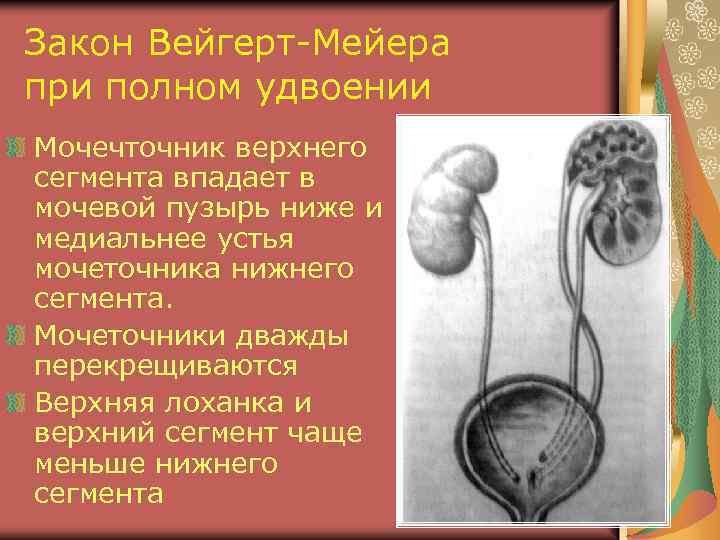

Закон Вейгерт-Мейера при полном удвоении Мочечточник верхнего сегмента впадает в мочевой пузырь ниже и медиальнее устья мочеточника нижнего сегмента. Мочеточники дважды перекрещиваются Верхняя лоханка и верхний сегмент чаще меньше нижнего сегмента